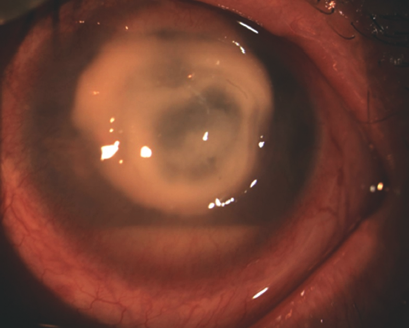

Biomicroscopy of the left eye revealed edema and hyperemia of the eyelids, as well as pronounced mixed injection of the eyeball, conjunctival chemosis, and in the optical and paraoptic zones of the cornea there was a white ring-shaped infiltrate with fuzzy contours and fusion in the center, d = 6.0 mm. The edges of the infiltrate reached the limbus in the vertical meridian. Reduced corneal sensitivity was found. The AC was shallower than in average. Opalescence of aqueous humor was “+++”, and 3 mm hypopyon was present. The pupil was round and in the center, d = 4.0 mm; there was no pupil reaction to light. Detailed ophthalmoscopy was difficult owing to the state of the cornea. A plain B-scan revealed no ultrasound pathology (Fig. 8).

Fig. 8. Patient K. Photo of the eye on admission

Рис. 8. Пациент К. Фото глаза при поступлении

In order to verify the diagnosis, a corneal confocal microscopy was performed with an HRT 3 device with a corneal module (Heidelberg Retina Tomograph Rostock Cornea Module). In the middle stroma of the stria there was an edema of the ground substances. Bright fusiform structures – pseudofilaments of Candida – and hyperreflective bilayer structures – Acanthamoeba cysts – were visualized in the layers of the middle stroma. The deeper layers of the cornea could not be visualized. The histopathology of the keratitis was of mixed (bacterial, Acanthamoeba, and fungal) etiology (Fig. 9). A washing from the cornea for Acanthamoebae was performed. Microscopy of the sediment revealed Acanthamoebae and bacteria; inoculation from the cornea and conjunctiva for the culture and sensitivity to antibiotics, on Sabouraud’s medium, was negative.